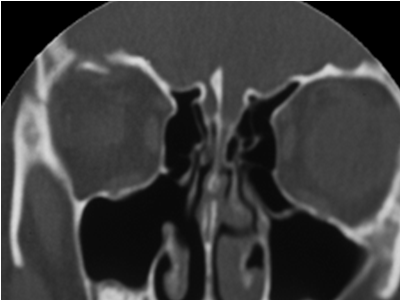

The gold standard for diagnosis of an orbital roof fracture is thin-cut coronal CT scanning of the face/orbits. Contrast is not needed. Although sagittal sections are also helpful in some cases, the axial images are less so. The CT scan will reveal the exact size and location of the fracture as well as associated fractures of the orbit, face and head. Other entities such as foreign bodies, hematoma, globe rupture and optic nerve trauma may also be found. 3D CT reconstruction can be performed, some find this a very helpful modality to define fractures of the orbital rim and frontal bone but generally does not add to the information from other CT images.